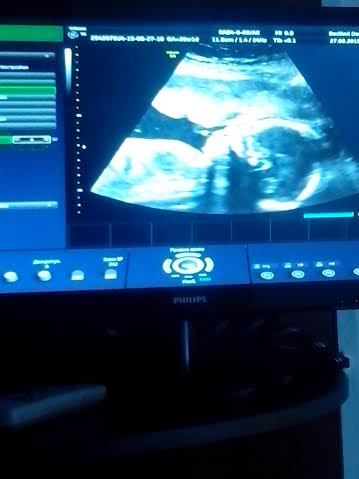

УЗИ, КТГ, доплерВсе хорошо, но ходили на бесплатное, врач так скоро все сделал что мы даже не увидели что ребенок шевелится или сердце стучит, ничего не показали дали только сфоткать. Если я бы не чувствовала шевеление то очень бы переживала.

Вес 340гр.

Сердце 146

околоплодные воды 43 мл.